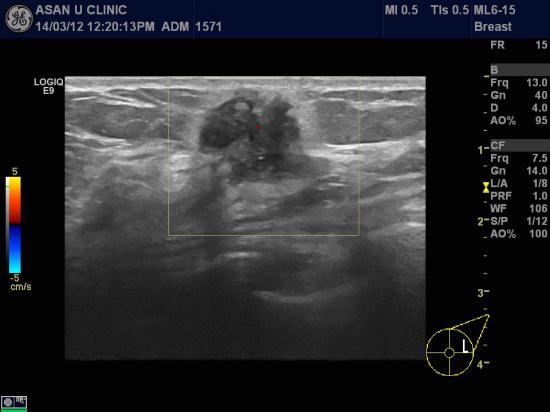

아산유외과 진료 후 75번째 유방암진단.

유방암 검진에서 이상소견있다고 의뢰된 62세 여성분입니다.

좌측유방 상외측에 1.6cm의 석회화포함한 결절이 있었고

같은 방향 겨드랑이에 비대된 림프절소견이 보입니다.

초음파 유도하에 유방종괴의 중심핵생검과

겨드랑이 림프절의 흡인세포검사하여

유방의 침윤성 유관암과 액와림프절의 암전이가 진단되어

유방의 MRI와 PET scan 예정입니다.

나이드셨다고 방심하지 말고 양측 유방과 양측 겨드랑이에 잡히는 것은 없는지

꼭 확인합시다.